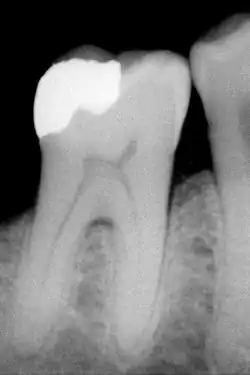

An X-ray showing enamel and dentin replaced by an amalgam restoration

Dental restorations

Most dental restorations involve the removal of enamel. Frequently, the purpose of removal is to gain access to the underlying decay in the dentin or inflammation in the pulp. This is typically the case in amalgam restorations and endodontic treatment.

The large amount of mineral in enamel accounts not only for its strength but also for its brittleness.[6] Tooth enamel ranks 5 on Mohs hardness scale (between steel and titanium) and has a Young's modulus of 83 GPa.[4] Dentin, less mineralized and less brittle, 3–4 in hardness, compensates for enamel and is necessary as a support.[7] On radiographs, the differences in the mineralization of different portions of the tooth and surrounding periodontium can be noted; enamel appears lighter than dentin or pulp since it is denser than both and more radiopaque.[8]